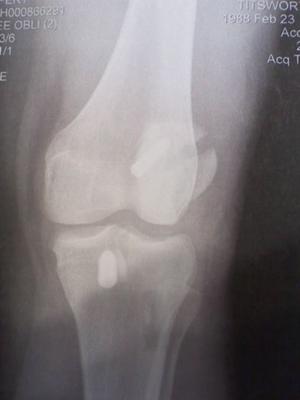

patella fracture after ACL reconsturction

Day 12 was a normal day until I was crossing the train tracks that run through the middle of campus, I tripped. I didn't fall but caught myself instead on my bad leg, I had immediate pain and couldn't move. My friends helped me into the backseat of one of their cars, I couldn't move my leg, bending it was excruciating, the pain was worse than when I tore my ACL and worse than after the surgery. I went to the ER and found out I fractured my patella. The doctor there made it seem like it wasn't a big deal and that a minor surgery would fix it, but he was wrong.

I went home the next day to see my doctor and she scheduled me for surgery the next day. Only 2 weeks from my ACLr I had to have an ORIF of my patella (2 screws). This surgery was 10x more painful than the first and I thought I would never feel better. I couldn't even take off my immobilizer to shower, I was only allowed to have it taken off 10 days later to have my 27 staples taken out. My life seemed to fall apart around me, I was depressed and lost a lot of weight and I couldn't sleep anymore.